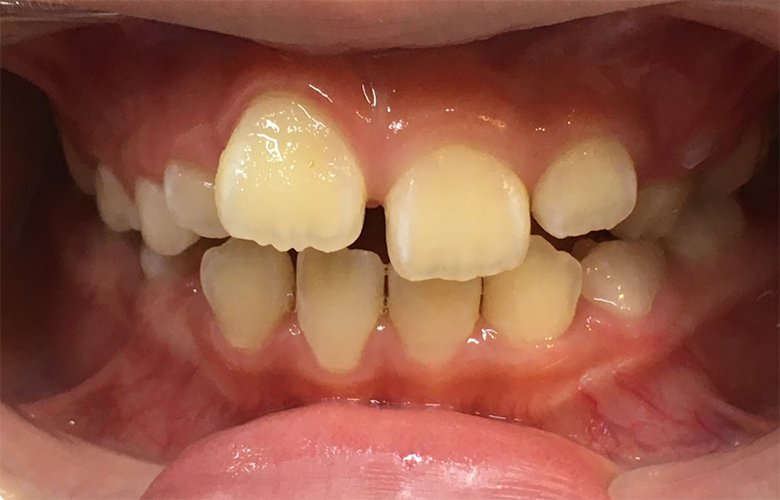

小児矯正(Ⅰ期治療)により将来の歯列スペースを確保した症例(7歳女児)

治療前 ![]() |

前歯の歯並びの乱れと噛み合わせのズレが気になるとのことで来院されました。永久歯への生え変わりを迎える時期であり、将来的な歯並びを整えるために早期の矯正相談を希望されました。 |

上下前歯部に叢生傾向が認められ、歯列弓の幅が不足している状態でした。このまま永久歯が萌出すると、歯の並ぶスペース不足により叢生が強くなる可能性がある状態でした。 |

成長期の顎の発育を利用した小児矯正(Ⅰ期治療)を行い、歯列の幅を拡大し永久歯が並ぶためのスペースを確保しました。混合歯列期(6EDC2112CDE6)の段階で適切な歯列弓を形成することを目的として治療を行いました。 |